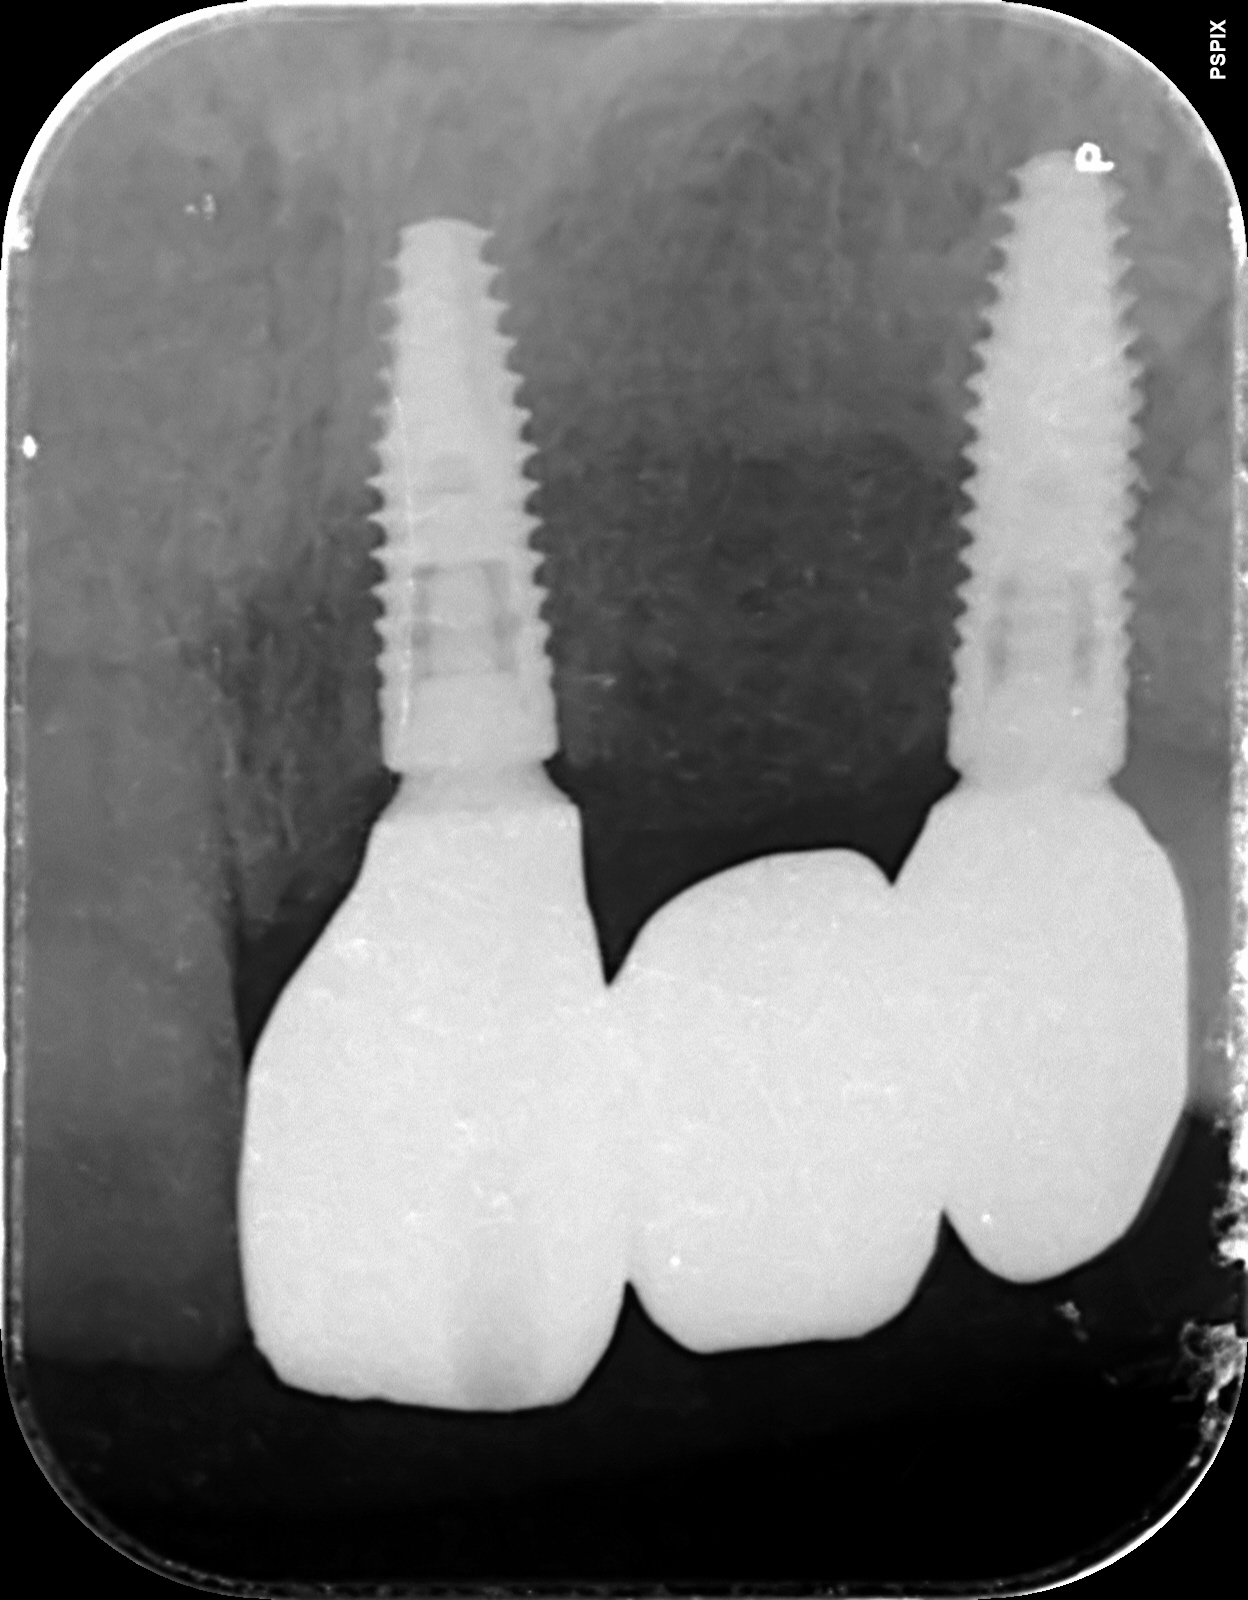

最終的にインプラント治療を希望され、施術させて頂きました。

術後

インプラント治療期間:約4か月

費用:¥1,177,000-(税込)

インプラント体 2本

インプラント上部構造物(セラミックブリッジ)

インプラントの仮歯